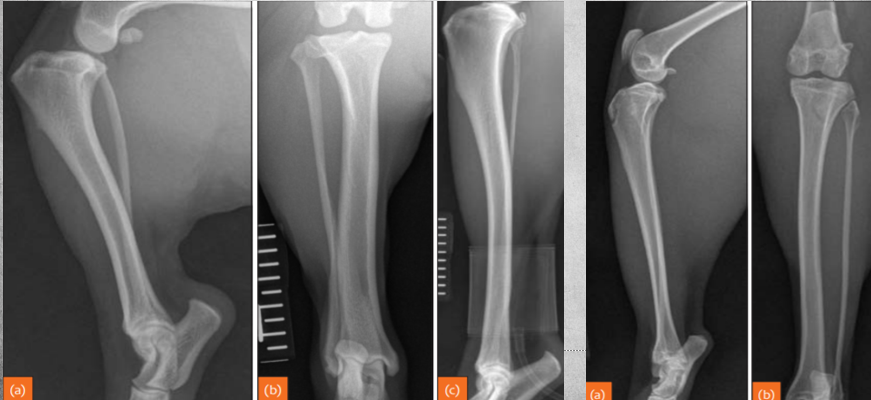

Q

identify left to right

A

left to right:

Transverse fracture

Oblique fracture

Spiral fracture